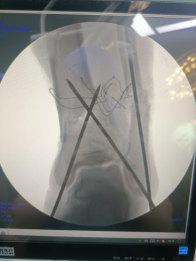

術(shù)中透視脛腓骨遠(yuǎn)端,予以克氏針臨時固定。